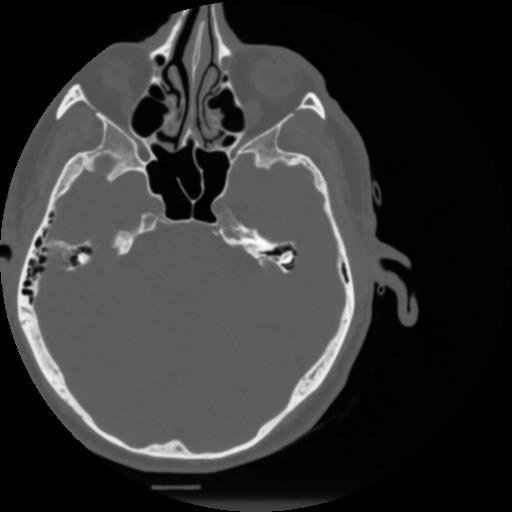

4 CEREBRO,,Vol,0.5,CEREBRO,,